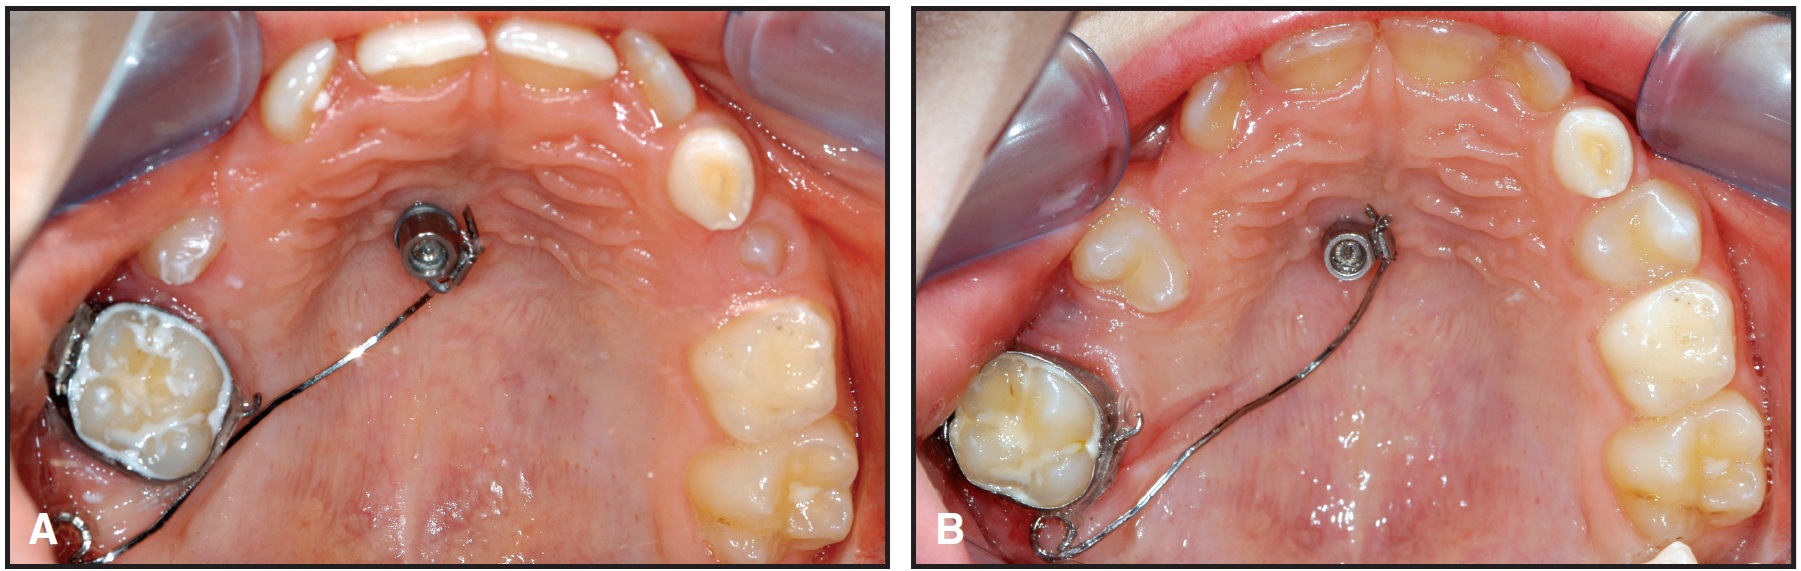

Fig. 5 Uprighting of mandibular left second molar with 2mm ï 11mm Benefit mini-implant and bracket abutment. A. Patient before molar uprighting. B. After four months of uprighting with .016" x .022" TMA segmental wires.

Fig. 7 Mesial space closure in patients with missing maxillary anterior teeth. A. Stainless steel wire bonded to lingual surfaces of maxillary central incisors and welded to Benefit abutment for indirect anchorage in bilateral space closure. B,C. Mesial Slider used for unilateral space closure and midline correction.